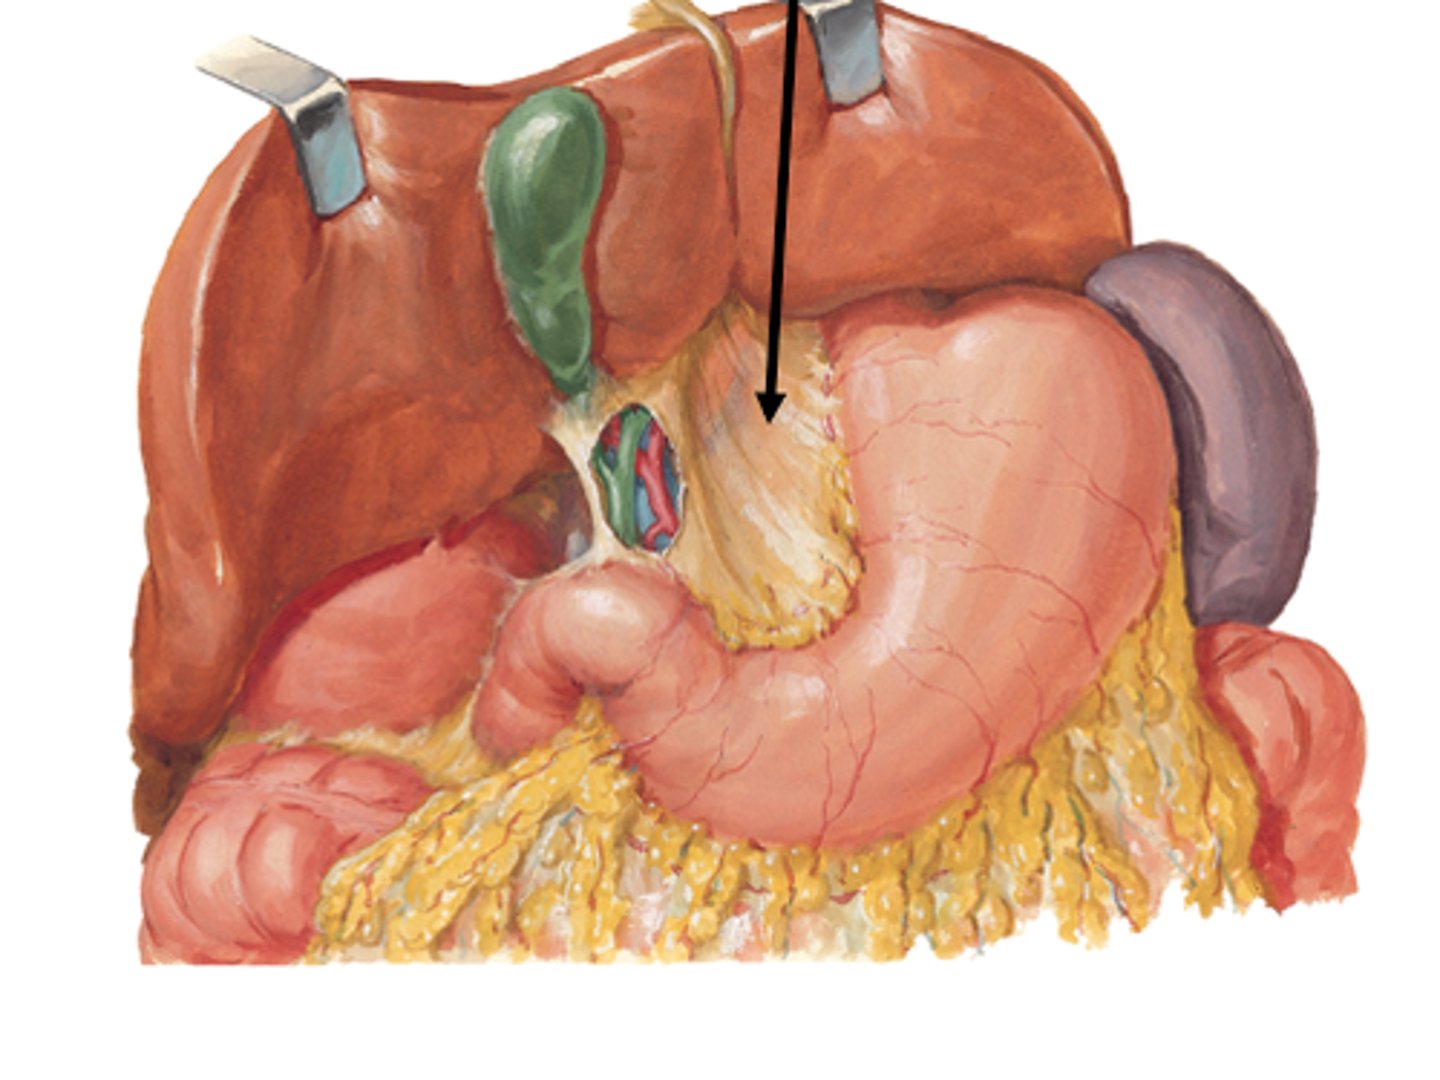

stomach

fundus

cardia

body

lesser curvature

greater curvature

cardiac sphincter / lower esophageal sphincter

pylorus

pyloric sphincter

rugae

lesser omentum

greater omentum

duodenum

liver

Gallbladder

pancreas

spleen